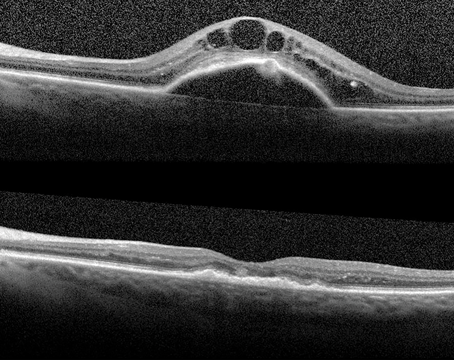

Retinal autograft with retinectomy and the SPOT technique for macular hole

The technique can be very useful in the setting of highly myopic PVR re-detachment.